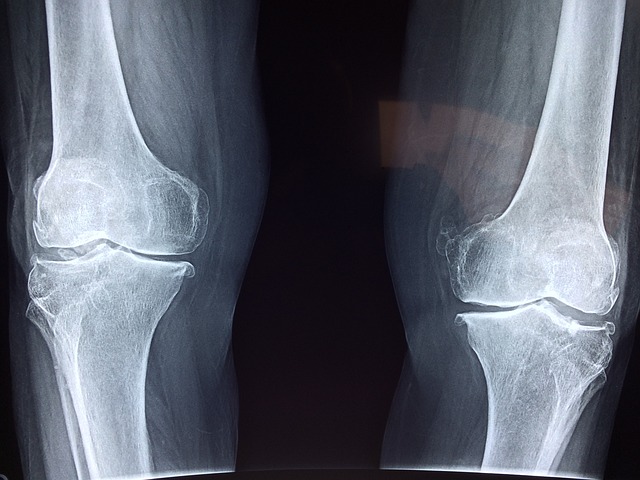

W przypadku osób z problemami ortopedycznymi, takimi jak płaskostopie, koślawość czy stopa cukrzycowa, buty ortopedyczne mogą być niezwykle pomocne. Poprawiają one biomechanikę stóp, redukując nacisk na poszczególne obszary i zapobiegając dalszym uszkodzeniom. Dzięki temu osoba nosząca buty ortopedyczne może chodzić bez większych trudności i bólu.